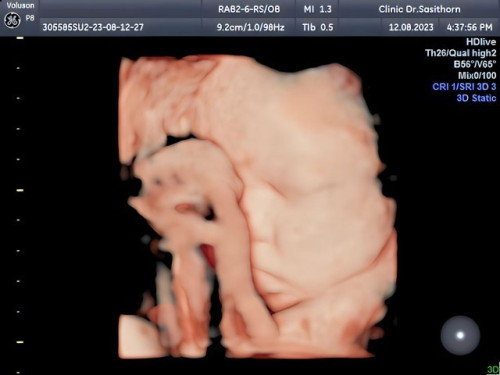

เครียดเรื่องนํ้าหนักลูก👩🍼

35+3 1897g #แข็งแรงทุกอย่างแต่ติดที่นํ้าหนัก😢🤰#มีบ้านไหนเป็นเหมือนกันบ้างมั้ยพยายามบำรุงทุกอย่างซื้อมากินทุกอันที่คนอื่นว่าดีแต่ก็ไม่เป็นผล🥲 #จนตอนนี้เครียดไม่อยากกินท้อไม่มีกำลังใจกังวลน้อยใจเหนื่อย😭 กังวลไปหมดทุกอย่างจะผ่าวันที่1กันยายนนี้แล้ว #แม่บ้านไหนนํ้าหนักลูกดีก็ดีไปแต่บ้านดีเครียดจนไม่มีความสุข ไม่รู้จะทำไงต่อ😓🤦♀️ #ขอบคุณสำหรับคำตอบค่ะ #ขอคำแนะนำหน่อยค่ะ 🙏